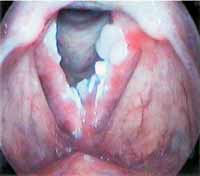

Alguns hábitos e condições podem agravar a papilomatose laríngea e devem ser evitados a todo custo. O tabagismo e o consumo excessivo de álcool são fatores de risco conhecidos para o câncer de cabeça e pescoço e podem piorar as lesões na laringe, como aponta o Portal Drauzio Varella. Além disso, o refluxo gastroesofágico pode levar a uma inflamação crônica na laringe, exacerbando a condição.

Entenda a Relação entre Tabagismo

Impacto do Refluxo Gastroesofágico na Laringe

O refluxo gastroesofágico é um fator que não pode ser ignorado quando falamos de saúde laríngea. O ácido que sobe do estômago pode irritar e inflamar cronicamente a laringe, criando um ambiente propício para a piora da papilomatose. O Instituto da Tireoide e Laringe destaca exatamente isso: o refluxo pode causar inflamação crônica na laringe. Controlar o refluxo através da dieta e, se necessário, com orientação médica, é fundamental.

O Impacto do Refluxo na Papilomatose Laríngea: Guia Completo

Referência: otorrinopaulista.com.br